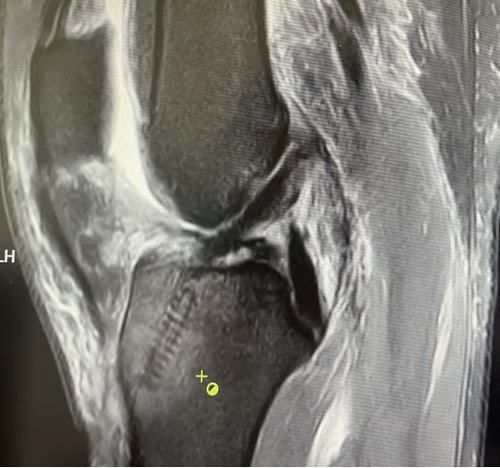

膝關節韌帶損傷磁共振

我院骨科三病區近期收治了4名膝關節交叉韌帶損傷患者。25歲的齊先生,因打籃球時不慎扭傷左膝,致右膝腫痛,遂來我院治療;30歲趙先生酷愛足球,扭傷右膝關節來我院就診;50歲的張先生、42歲劉先生因騎車滑倒摔傷、膝關節腫痛不適、活動受限,收治入院。骨科三病區李鵬主任團隊詳細查體以及完善影像學檢查后進行診斷:幾位患者共同診斷均有“前交叉韌帶損傷”,不同程度合并有“半月板損傷”、“股骨軟骨損傷”、“內側副韌帶斷裂”。